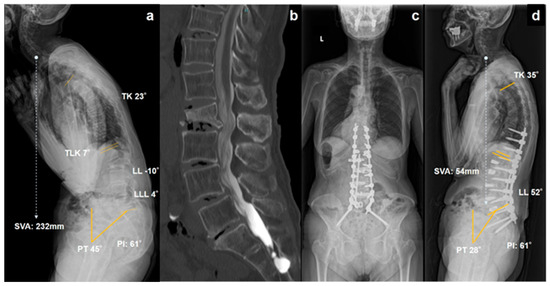

25 February 2026

Background: Kyphotic deformity following osteoporotic vertebral fracture (KDOVF) often requires corrective surgery to restore sagittal alignment; however, mechanical complications, such as proximal junctional failure (PJF) and distal junctional failu...